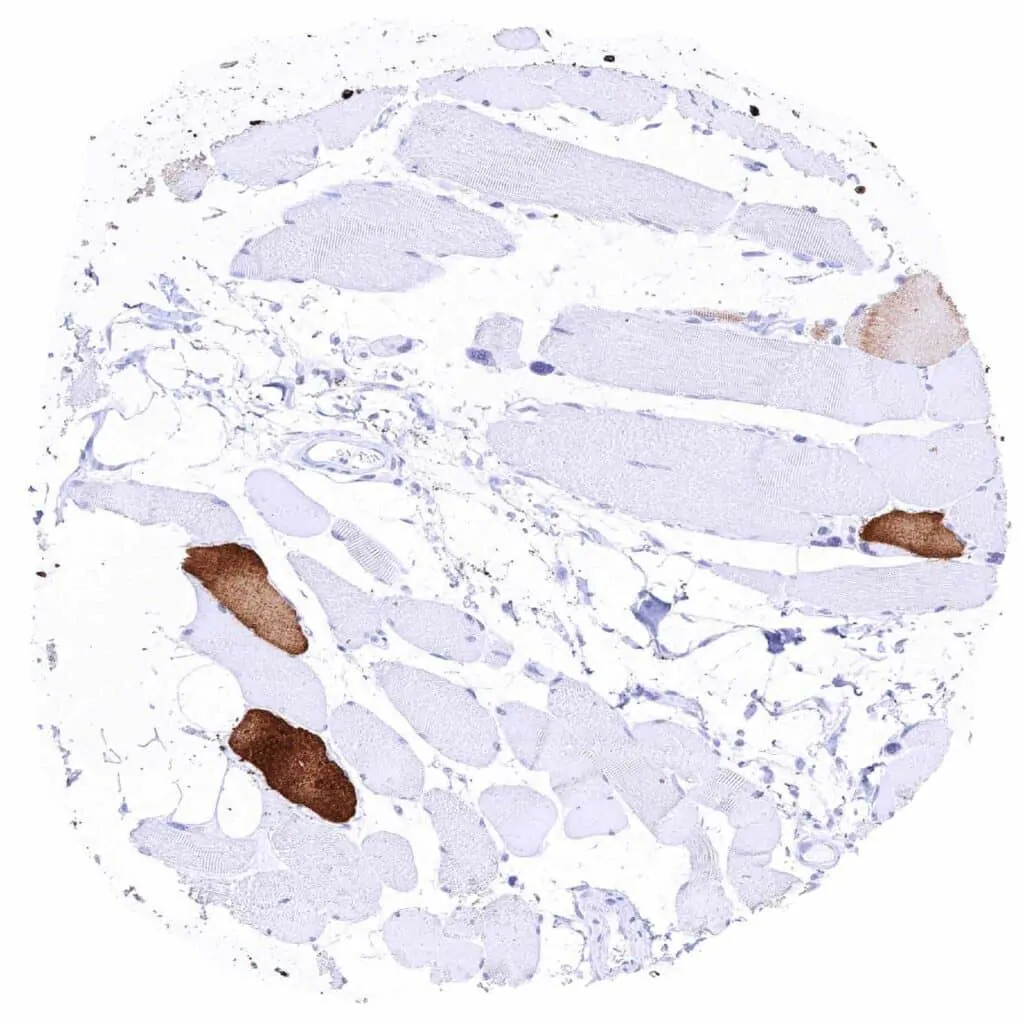

Skeletal muscle – Strong cytoplasmic MYH7 staining of a subset of muscular cells

Skeletal muscle – Strong cytoplasmic MYH7 staining of about half of muscular cells

Skeletal muscle – Strong cytoplasmic MYH7 staining of most muscular cells

Skeletal muscle – Variable intensity cytoplasmic MYH7 staining of a subset of muscular cells